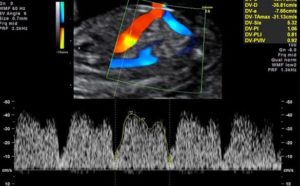

Венозный проток (ВП). Изучается при расширенной допплеровской оценке кровотока.

Для оценки венозного протока не используют индексы.

Диагностическим критерием патологического состояния плода считается наличие отрицательных или нулевых значений кровотока в фазу сокращения предсердий. Нулевые или реверсивные значения регистрируются при гипотрофии плода, врождённых пороках правых отделов сердца, неиммунной водянке плода.

Даже при критическом кровотоке в артериях пуповины, но при сохранённом кровотоке в венозном протоке в фазу сокращения предсердий, возможно продление вынашивания до оптимальных сроков для родов.